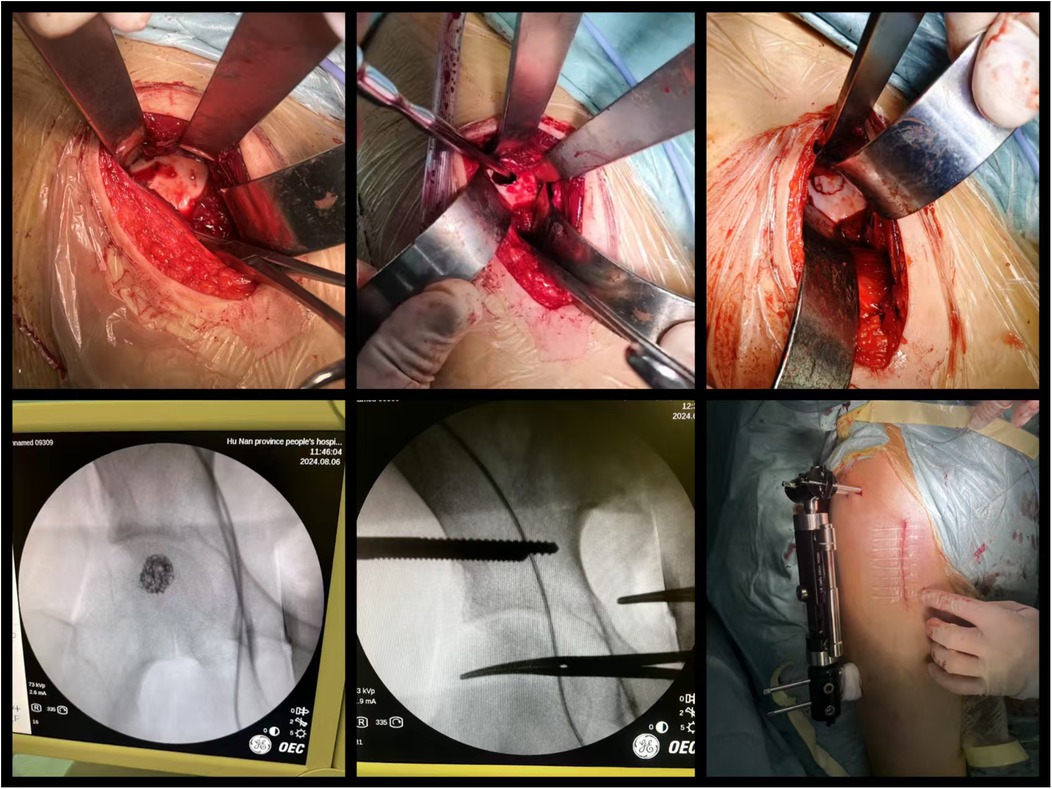

Biopsy examination confirmed a chondroblastic mesenchymal tumor in the right femoral head lesion. Based on the patient's clinical history, physical findings,aforementioned imaging studies, and biopsy result, the preoperative diagnosis was formulated as Bone lesion in the right femoral head of uncertain nature: (1) Chondroblastoma, (2) Right hip joint synovitis. Following completion of preoperative preparation, a direct anterior approach (DAA) was performed to access the right hip joint, with an approximately 8 cm longitudinal incision. After skin incision was made, the lateral femoral cutaneous nerve was carefully dissected and preserved. The surgical plane between the sartorius and tensor fascia lata muscles was developed, and the rectus femoris muscle was gently retracted medially to expose the joint capsule. A T-shaped capsulotomy and trapdoor was performed, the cartilage above the lesion of femoral head was designed a round door, the posterior quarter of the round door was preserved as a hinge of the trapdoor. Intraoperative manipulation revealed a round osteolytic lesion within the femoral head measuring approximately 1.5 cm  ×  1.5 cm Viable lesion tissue was identified and thoroughly curetted (Figure 2). After complete debridement, allogeneic bone grafting was performed. Intraoperative C-arm fluoroscopy confirmed satisfactory placement of the bone graft. Two screws (5.0 mm × 150 mm) were then inserted into the ilium and two screws(5.0 mm × 150 mm) into femur respectively, and an external fixation frame was assembled(Carefix, Shanghai, China. http://www.carewayer.com/). Traction was applied to the femoral head to relieve intra-articular pressure and ensure joint stability. Once optimal alignment and tension were achieved, the external fixation frame was secured. We only did once traction during the entire treatment progress, the traction was done intra-operation and the distance is 5 mm. The wound was irrigated copiously, hemostasis was ensured, and the incision was closed in layers. Sterile dressings were applied postoperatively. Based on histomorphology, immunohistochemical profile (S-100(+), p63(partial +), CK(pan)(−), CK8/18(−), DOG1(partial +), Ki67(+, 5%), p53(scattered +), SATB2(partial +), MDM2(small foci +), CDK4(small foci +), H3.3G34W(−), H3K36M(+), Ki67(5%+), MDM2(osteoclast+), P53(10%+)), and clinical presentation, chondroblastoma was diagnosed (Figure 3). As the purpose of the arthrodiastasis is to relieve intra-articular pressure and ensure joint stability, we did NOT set a articulated hinge for the hip joint but just a fixation. The patient was asked non-weightbearing until the external fixation was removed. The external fixation frame was removed after a two-month follow-up period to adequately alleviate pressure on the femoral head.

Figure 3

Surgical procedure with multiple images showing detailed steps. Top row: incision and bone exposure with retractors. Bottom row: X-rays showing internal views with tools, and a final image depicting sutured incision on a patient's leg, partially covered with blue drapes.

Figure 3. Intraoperative images.